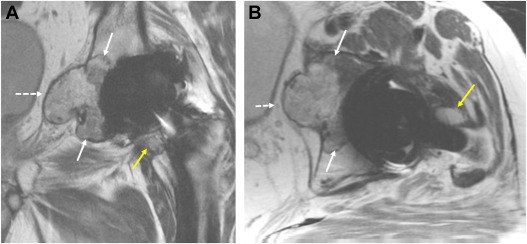

Ultrasound features of tophi in chronic tophaceous gout.

Skeletal Radiol. 40: 309-315Yu J.S. Chung C. Recht M. et al.

MR imaging of tophaceous gout.

AJR Am J Roentgenol. 168: 523-527